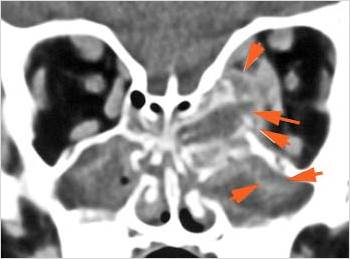

Orbits

The extraconal orbital fat is abnormal.

There is a subperiosteal abscess or edema along the medial wall, roof or floor of the orbit.

The extraocular muscles are swollen or otherwise abnormal.

There is bone erosion along the walls of the orbit.